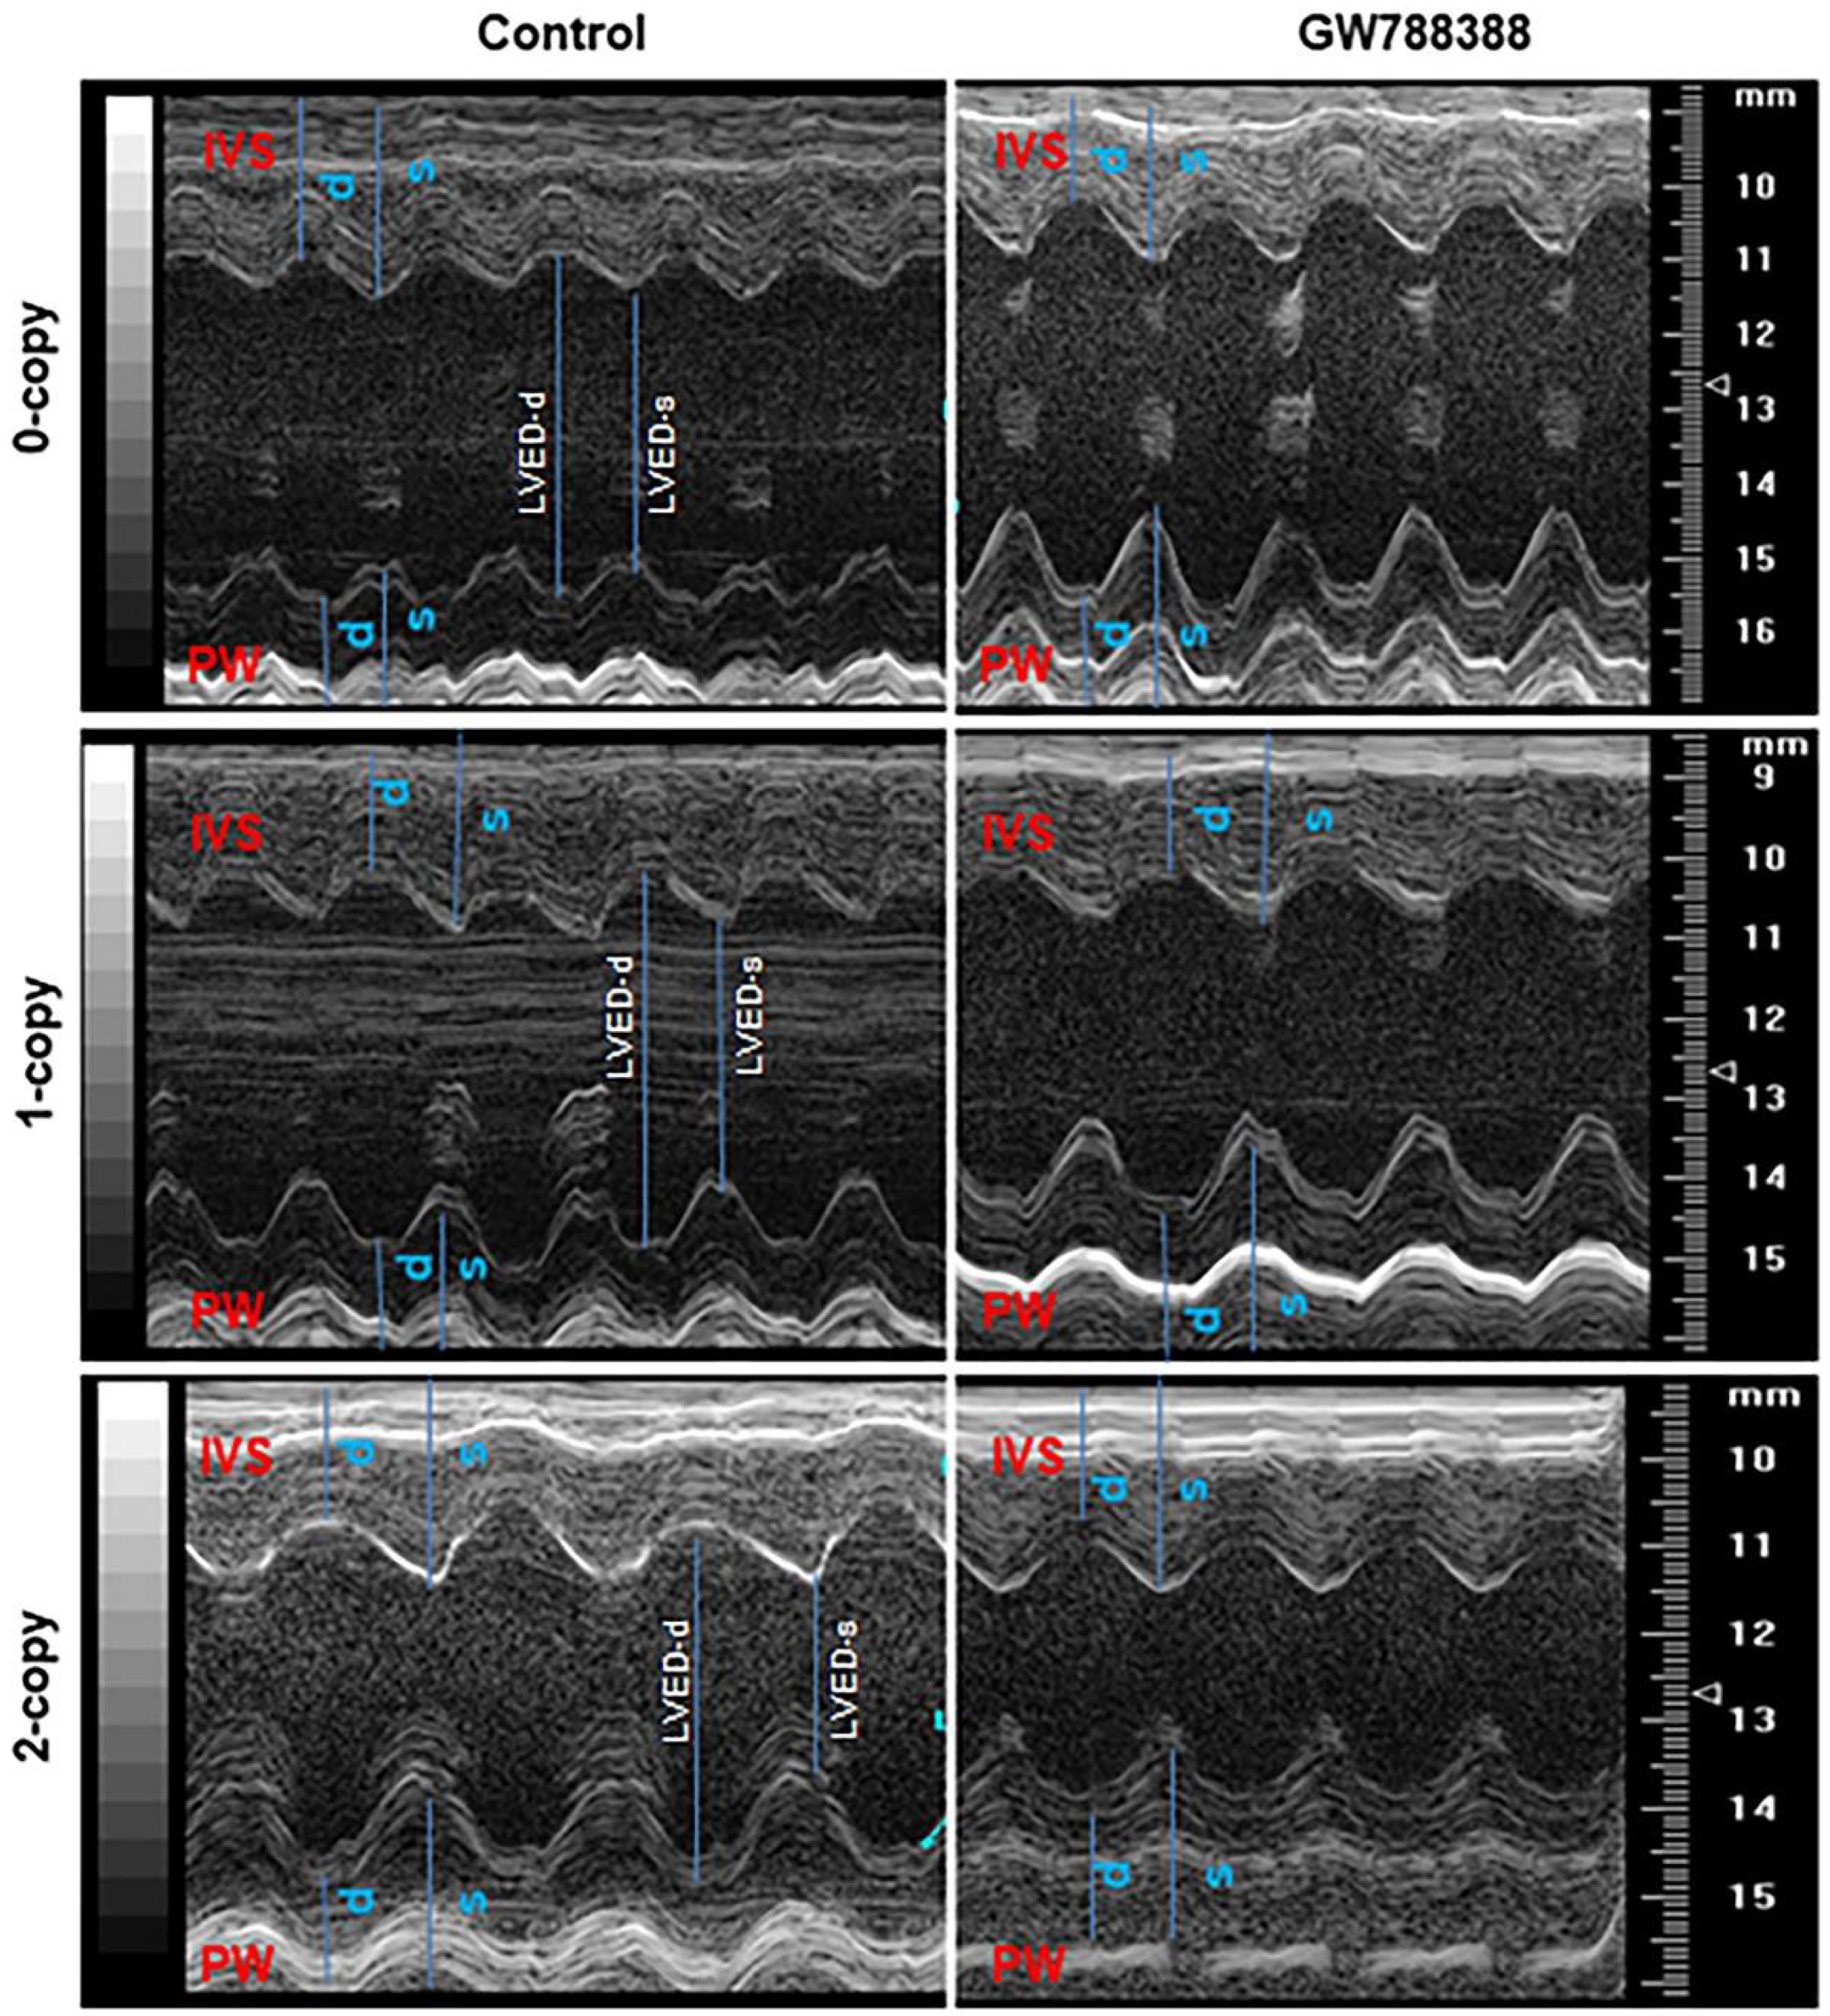

2.6. Treatment of Npr1−/− Mice with GW788388 Attenuates Systolic BP and Cardiac Dysfunction in a Sex-Dependent Manner

2.8. Differential Hemodynamic Parameters and Echocardiographic Functional Outcome in Male and Female Mutant Mice